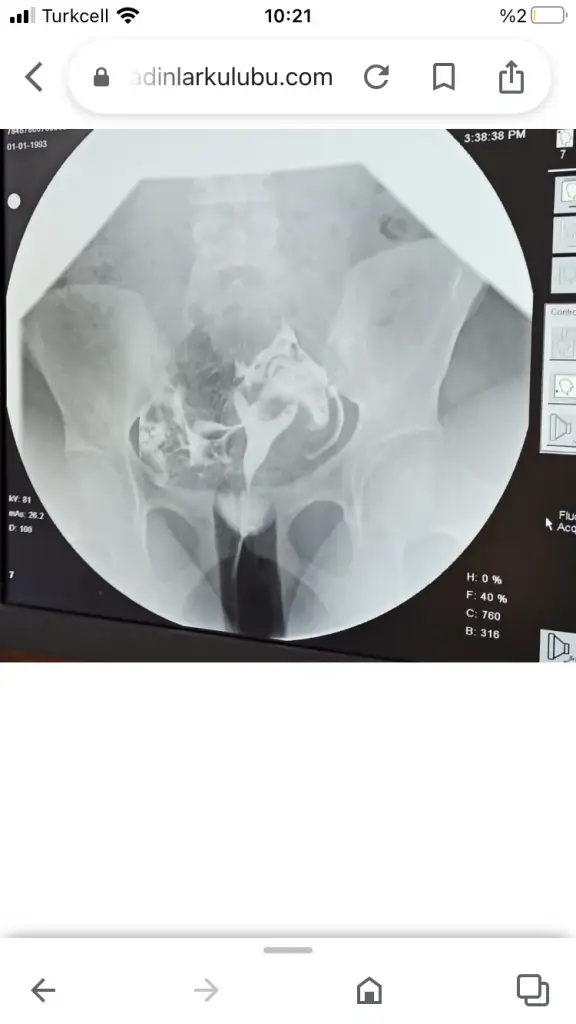

Benim görüntü buydu